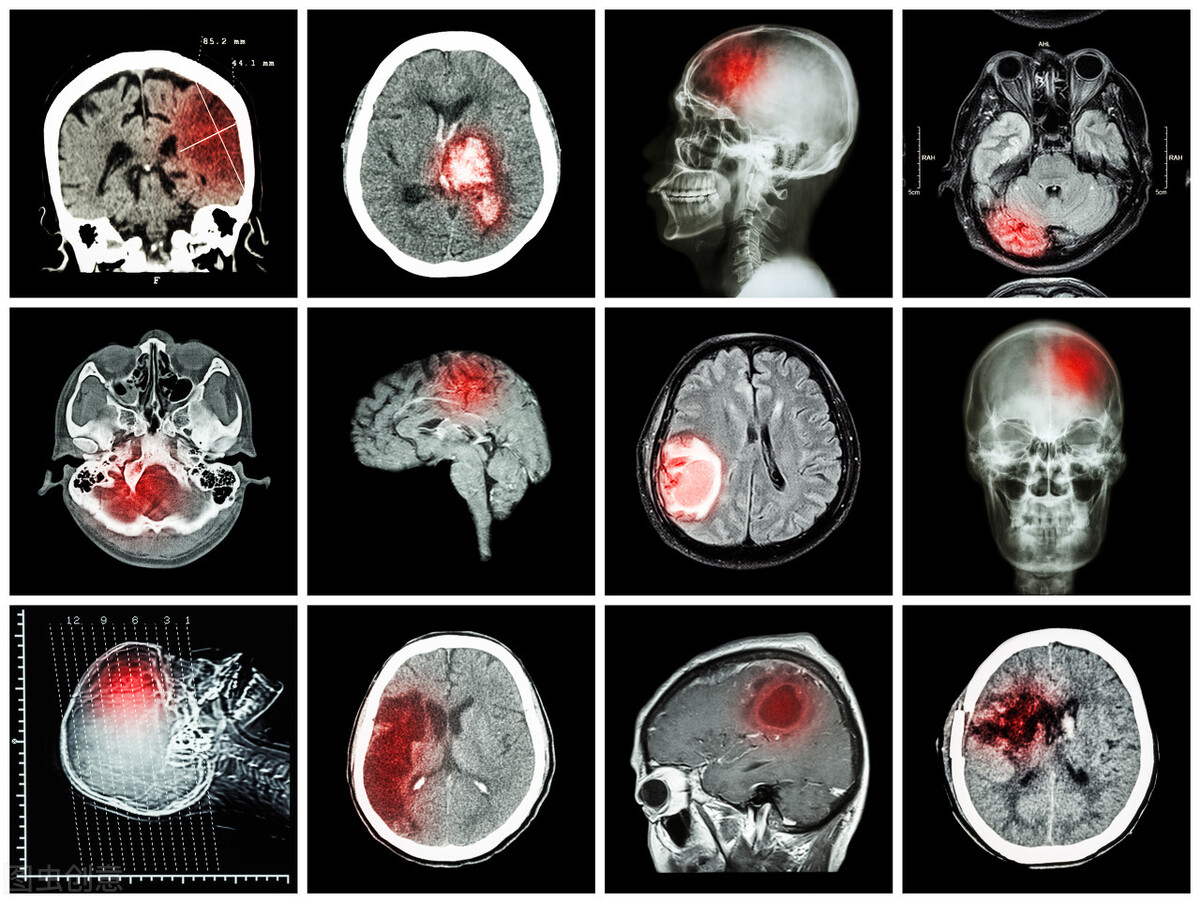

发生了眩晕、耳鸣不一定是突聋导致的,还可能是其他的病变,有些可能是脑部病变导致的,所以要注意区分。

其一,区分大脑中枢性疾病,比如说突发性的脑梗塞、脑瘀血,如果是这种原因引起的耳部异常,还可能同时伴有恶心、呕吐、眩晕等。这些病变有时是致命性的,尤其需要争分夺秒地进行治疗。

如果是有高血压、糖尿病等基础疾病的中老年患者出现了眩晕,优先考虑到神经内科去就诊,先排除大脑中枢神经性的病变。

第二个,还可能引起相似症状的疾病是听神经瘤。听神经瘤生长在耳朵与大脑间的听神经上,是种良性肿瘤,随着肿瘤的增长会侵犯到周围的结构而导致听力下降,同时还可能伴随有耳鸣、眩晕的症状,要区别它,通常需要进行耳部的核磁共振检查来进行明确。